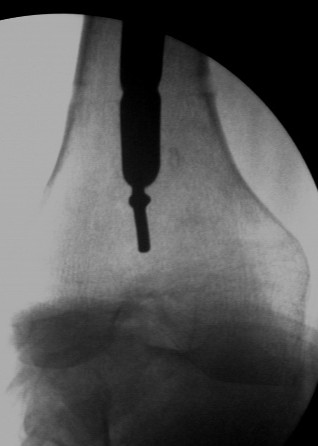

This is the C-arm picture before attemting to pull out thro the proximal end by hammering on a chuck.

Did not work out. The nail was a slotted one. The guidewire split the slot and came out but not the nail. Ultimately as mentioned in an earlier mail, I had to introduce a cannulated nail from distally threadind on the guide wire and hammer on the stuck nail and finally got it out